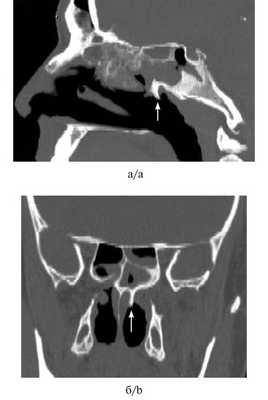

Больной Ф., 17 лет, поступил в ЛОР-клинику в январе 2016 г. по поводу отсутствия дыхания через левую половину носа, ринореи, постназального затека. Считает себя больным в течение 6 мес. В сентябре 2015 г. обращался с подобными жалобами к оториноларингологу, однако при осмотре в полости носа патологических изменений не выявлено; на СКТ от 09.09.2015 была обнаружена киста левой верхнечелюстной пазухи (рис. 2, а, б).

Рис. 2. СК-томограмма больного Ф. а, б — СКТ от 09.09.2015: определяется киста левой верхнечелюстной пазухи, полость носа свободна; в, г — СКТ от 12.01.2016: имеется киста и АХП.

В январе 2016 г. при проведении передней риноскопии и эндоскопического исследования у больного обнаружен АХП слева. На СКТ околоносовых пазух от 12.01.2016 выявлен АХП, исходящий из левой верхнечелюстной пазухи (см. рис. 2, в, г). Полип был удален эндоскопически.

Данный случай интересен тем, что нам удалось документировать срок, в течение которого полип распространился из верхнечелюстной пазухи в полость носа, а затем и в хоану. Для этого потребовалось 4 мес.